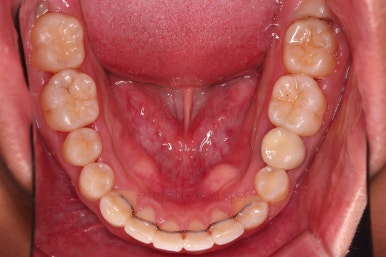

초진 시 입안의 모습입니다.

부정교합이 있고요.

윗니와 아랫니가 앞뒤로 지그재그 서로서로 껴있어야 좋은 교합인데 전반적으로 윗니가 앞으로 밀려있는 양상의 교합이에요.

또한 눈에 띄는 모습은 앞니가 튀어나오고, 사이사이 틈새가 보인다는 점이에요.

치열이 매우 가지런해졌고 틈새도 없어졌으며 교합도 잘 맞아졌어요.

사이가 다시 벌어지거나 틀어지지 말라고 치아 안쪽면으로 부착형 철사 유지장치를 붙이고 마무리를 했어요.